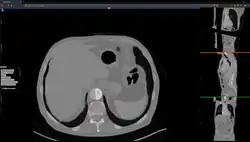

Studierfenster or StudierFenster (SF)[1][2][3] is a free, non-commercial open science client/server-based medical imaging processing online framework. It offers capabilities, like viewing medical data (computed tomography (CT), magnetic resonance imaging (MRI), etc.) in two- and three-dimensional space directly in the standard web browsers, like Google Chrome, Mozilla Firefox, Safari, and Microsoft Edge. Other functionalities are the calculation of medical metrics (dice score[4] and Hausdorff distance[5]), manual slice-by-slice outlining of structures in medical images (segmentation[6][7]), manual placing of (anatomical) landmarks in medical image data, viewing medical data in virtual reality, a facial reconstruction and registration of medical data for augmented reality,[8] one click showcases for COVID-19 and veterinary scans, and a Radiomics module.

The file converter converts a medical volume file (e.g. a non-compressed .nrrd file) to a compressed/binary .nrrd file. After the conversion, the compressed .nrrd file can be downloaded and used with the "Medical 3D Viewer" for 2D and 3D visualization, and further image processing.